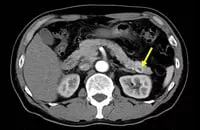

CT画像(インスリノーマ例)**

**:腫瘍を矢印で示す